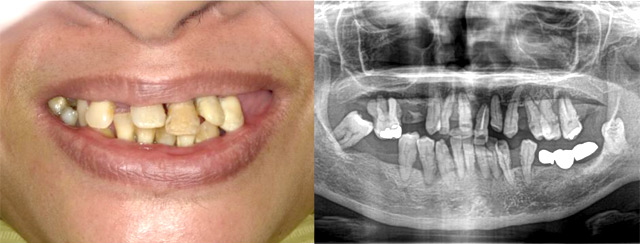

施行名 : 審美歯科(虫歯などをインプラント体によって改善する施術)

副作用やリスク : 麻酔で腫れやむくみを生じる場合があります。

また、劣化や口内の手入れを怠ることにより脱落する場合があります。

施術の価格:8万〜90万(税抜き)

※個人差があり、効果を保障するものではありません